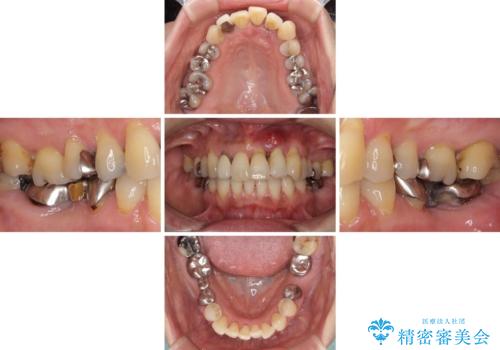

- 前歯の歯肉の腫れを気にして来院された患者様です。

前歯のみならず、奥歯の銀歯や下顎前歯のデコボコなど、色々と気になる部分を治したいとのことでした。

前歯は抜歯が必要であったので、抜歯を行い、その後歯肉移植をおこなった上でオールセラミックブリッジによる補綴治療を行うこととしました。

下顎と上顎臼歯部については矯正治療を行い、奥歯の欠損部位はオールセラミックブリッジを、その他の銀歯はセラミックインレーなどにより治療を行うこととしました。

気になっている部分を全て治療したことで、費用はかかりましたが、仕上がりには大変満足していただき、治療をおこなって良かったと仰っていただきました。